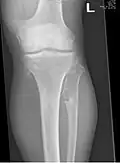

Multiple osteochondromas at the pelvis -

Multiple osteochondromas around the knee -